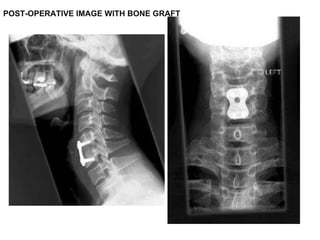

Surgery performed was an anterior cervical discectomy and fusion using the patients’ iliac bone.  I decided to fuse at two levels C4/C5 and C5/C6 though the main focus was really to do a good decompression of the space behind the C5/C6 disc, which is the site of maximal compression on the MRI scan.

POST OPERATIVE X-RAY

Post operative image The patient had an ACDF at C4/C5 and C5/C6. The kyphosis is corrected and hopefully will be maintained until fusion in the hard collar.  She will wear the collar for 3 months.

Clinically she recovered well from surgery and has been discharged home.  Her neurology has improved significantly with better sensation and increase in dexterity in the fingers.

Surgery performed wasan anterior cervical discectomy and fusion using the patients’ iliac bone. I decided to fuse at two levels C4/C5 and C5/C6 though the main focus was really to do a good decompression of the space behind the C5/C6 disc, which is the site of maximal compression on the MRI scan.

Post operative imageThe patient had an ACDF at C4/C5 and C5/C6. The kyphosis is corrected and hopefully will be maintained until fusion in the hard collar. She will wear the collar for 3 months.

Clinically she recoveredwell from surgery and has been discharged home. Her neurology has improved significantly with better sensation and increase in dexterity in the fingers.